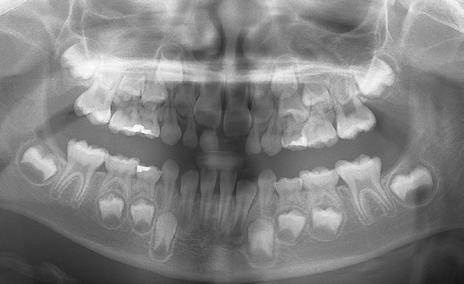

The panoramic radiograph (Figure 3) confirms a favorable difference in size between the primary second molars and permanent second premolars. Although a cursory evaluation of maxillary arch length does not appear to be as good as the available space in the mandible, expansion of the maxilla will obviously be required and generate more space.

The cephalometric radiograph and analysis (Figure 4a and Figure 4b) confirm a mild Class III skeletal relationship (ANB 1). The erupting maxillary incisors are retroclined and the mandibular incisors are proclined, contributing to the negative overjet.